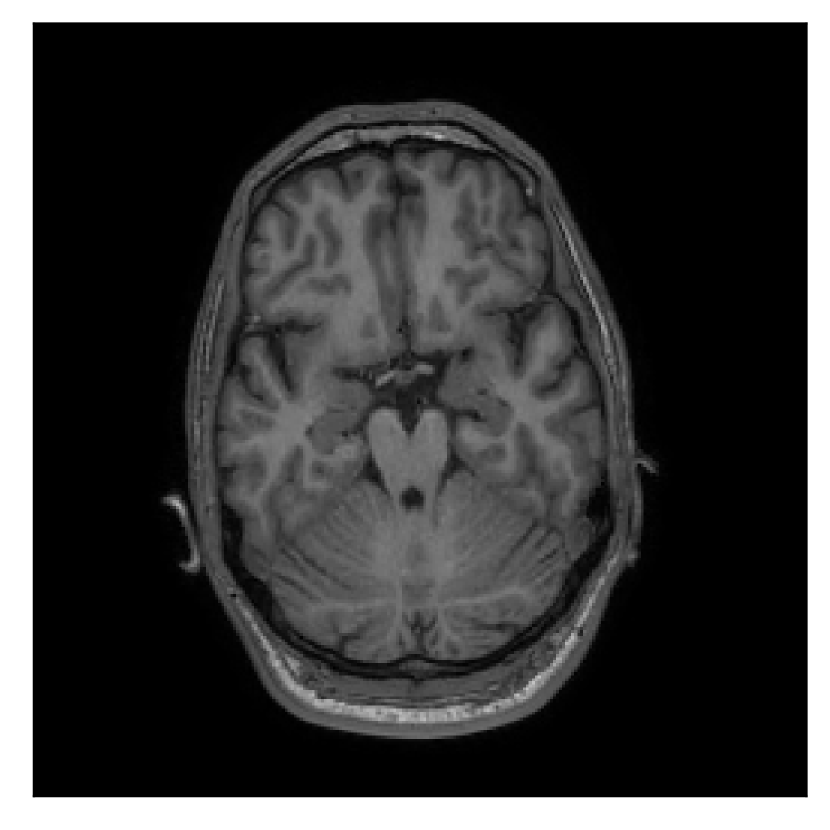

4.1 Experiment 1: robustness test

We gather the results for the robustness test described in Section 3.1 (volunteer 1) in Figures 2, 4, and 6 for motion corruption mechanisms associated to one, two, and five changes of position, respectively. Furthermore, we juxtapose the corrected images with varying degrees of corruption in Figure 8. We observe that the proposed method consistently ameliorates the corrupted scan. The quality indexes based on PSNR and SSIM show only a modest decrease in correction quality as a function of motion complexity (Figure 8).

| Section 3.1, Figure 2 | Sagittal | 23.94 | 27.95 | 0.7068 | 0.7936 |

| Coronal | 26.66 | 29.82 | 0.7653 | 0.8332 | |

| Axial | 25.40 | 30.16 | 0.7616 | 0.8490 | |

| Section 3.1, Figure 2 | T2-FLAIR | Completely corrected | Some blurring | No additional artifacts | Good grey white matter differentiation |

Sagittal

Coronal

Axial

Axial detail